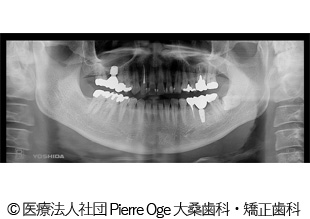

【症例2】左上34、左下5 インプラント治療

- 治療前

- 治療後

- 治療名

- 左上34、左下5 インプラント治療

- 費用

- 1,358,000円(税込)

- 費用の詳細

- 検査代:32,000円(税込)/手術代:690,000円(税込)/補綴代:636,000円(税込)

※当時の金額 - 期間

- 1年1ヵ月

- 通院回数

- 10回

- 性別・年齢

- 40代男性

治療内容

-

患者様の症状

重度の虫歯。インプラント治療希望でご来院されました。

治療方法

重度の虫歯になった歯を抜き、代わりにインプラントを埋入。骨量が少なかったため同時に人工骨移植。その日に仮歯まで装着。その後、インプラントが安定してから本物の被せ物を入れることで機能面・審美面の回復に繋がりました。

治療結果

重度の虫歯を補うことができ、機能面・審美面の回復に繋がりました。

治療を行う上での注意点(リスク・副作用)

疼痛、腫脹、青アザ、出血、神経麻痺、鼻出血、補綴物の破損、インプラント体の破折、咬合違和感、インプラント周囲炎。